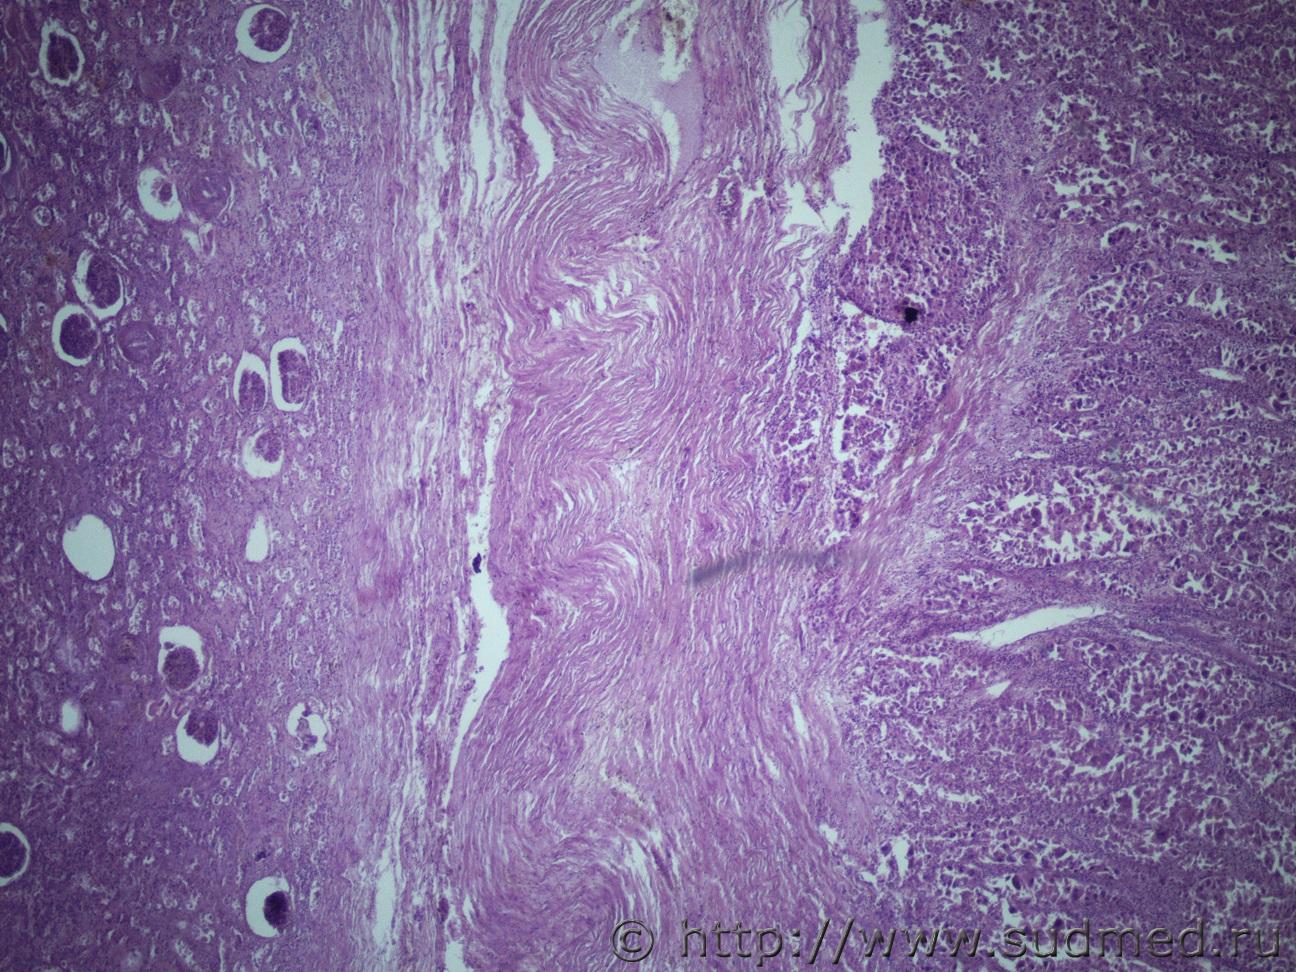

Ув. коллеги нужна помощь. Муж 60 лет. Эксперт присылает злокачественное новообразование левой почки с метастазами в правую почку и легкие. В стеклах опухоль в почке над капсулой (какая это почка правая или левая не указано) Судебная медицина - Прикрепленное изображение Судебная медицина - Прикрепленное изображениеСудебная медицина - Прикрепленное изображениеСудебная медицина - Прикрепленное изображениеСудебная медицина - Прикрепленное изображение

По мне - железистый вариант гипернефроидного рака.

Гипернефроидный рак.

Почечно медуллярная карцинома с mts в легкие